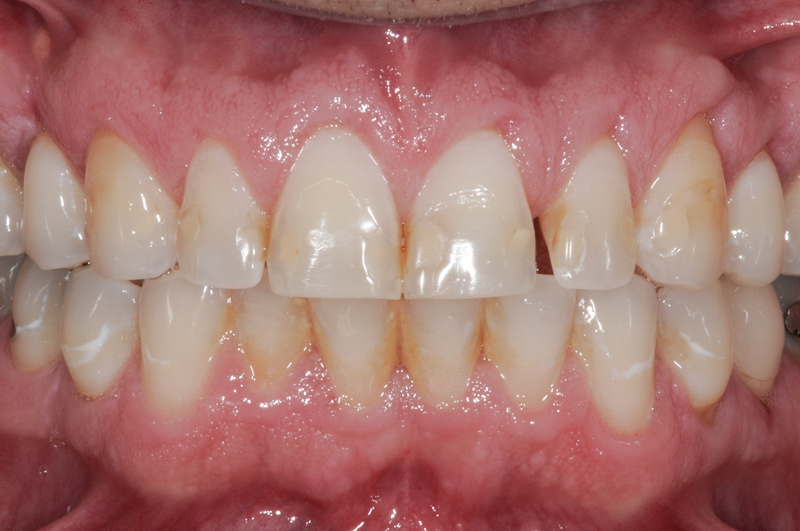

Fig 5. Preoperative view of patient requiring esthetic changes up to at least the bicuspids (Fig 5); postoperative view with CL-I feldspathic porcelain veneers up to the first bicuspid (Fig 6).

Figure 5

Fig 6. Preoperative view of patient requiring esthetic changes up to at least the bicuspids (Fig 5); postoperative view with CL-I feldspathic porcelain veneers up to the first bicuspid (Fig 6).

Figure 6